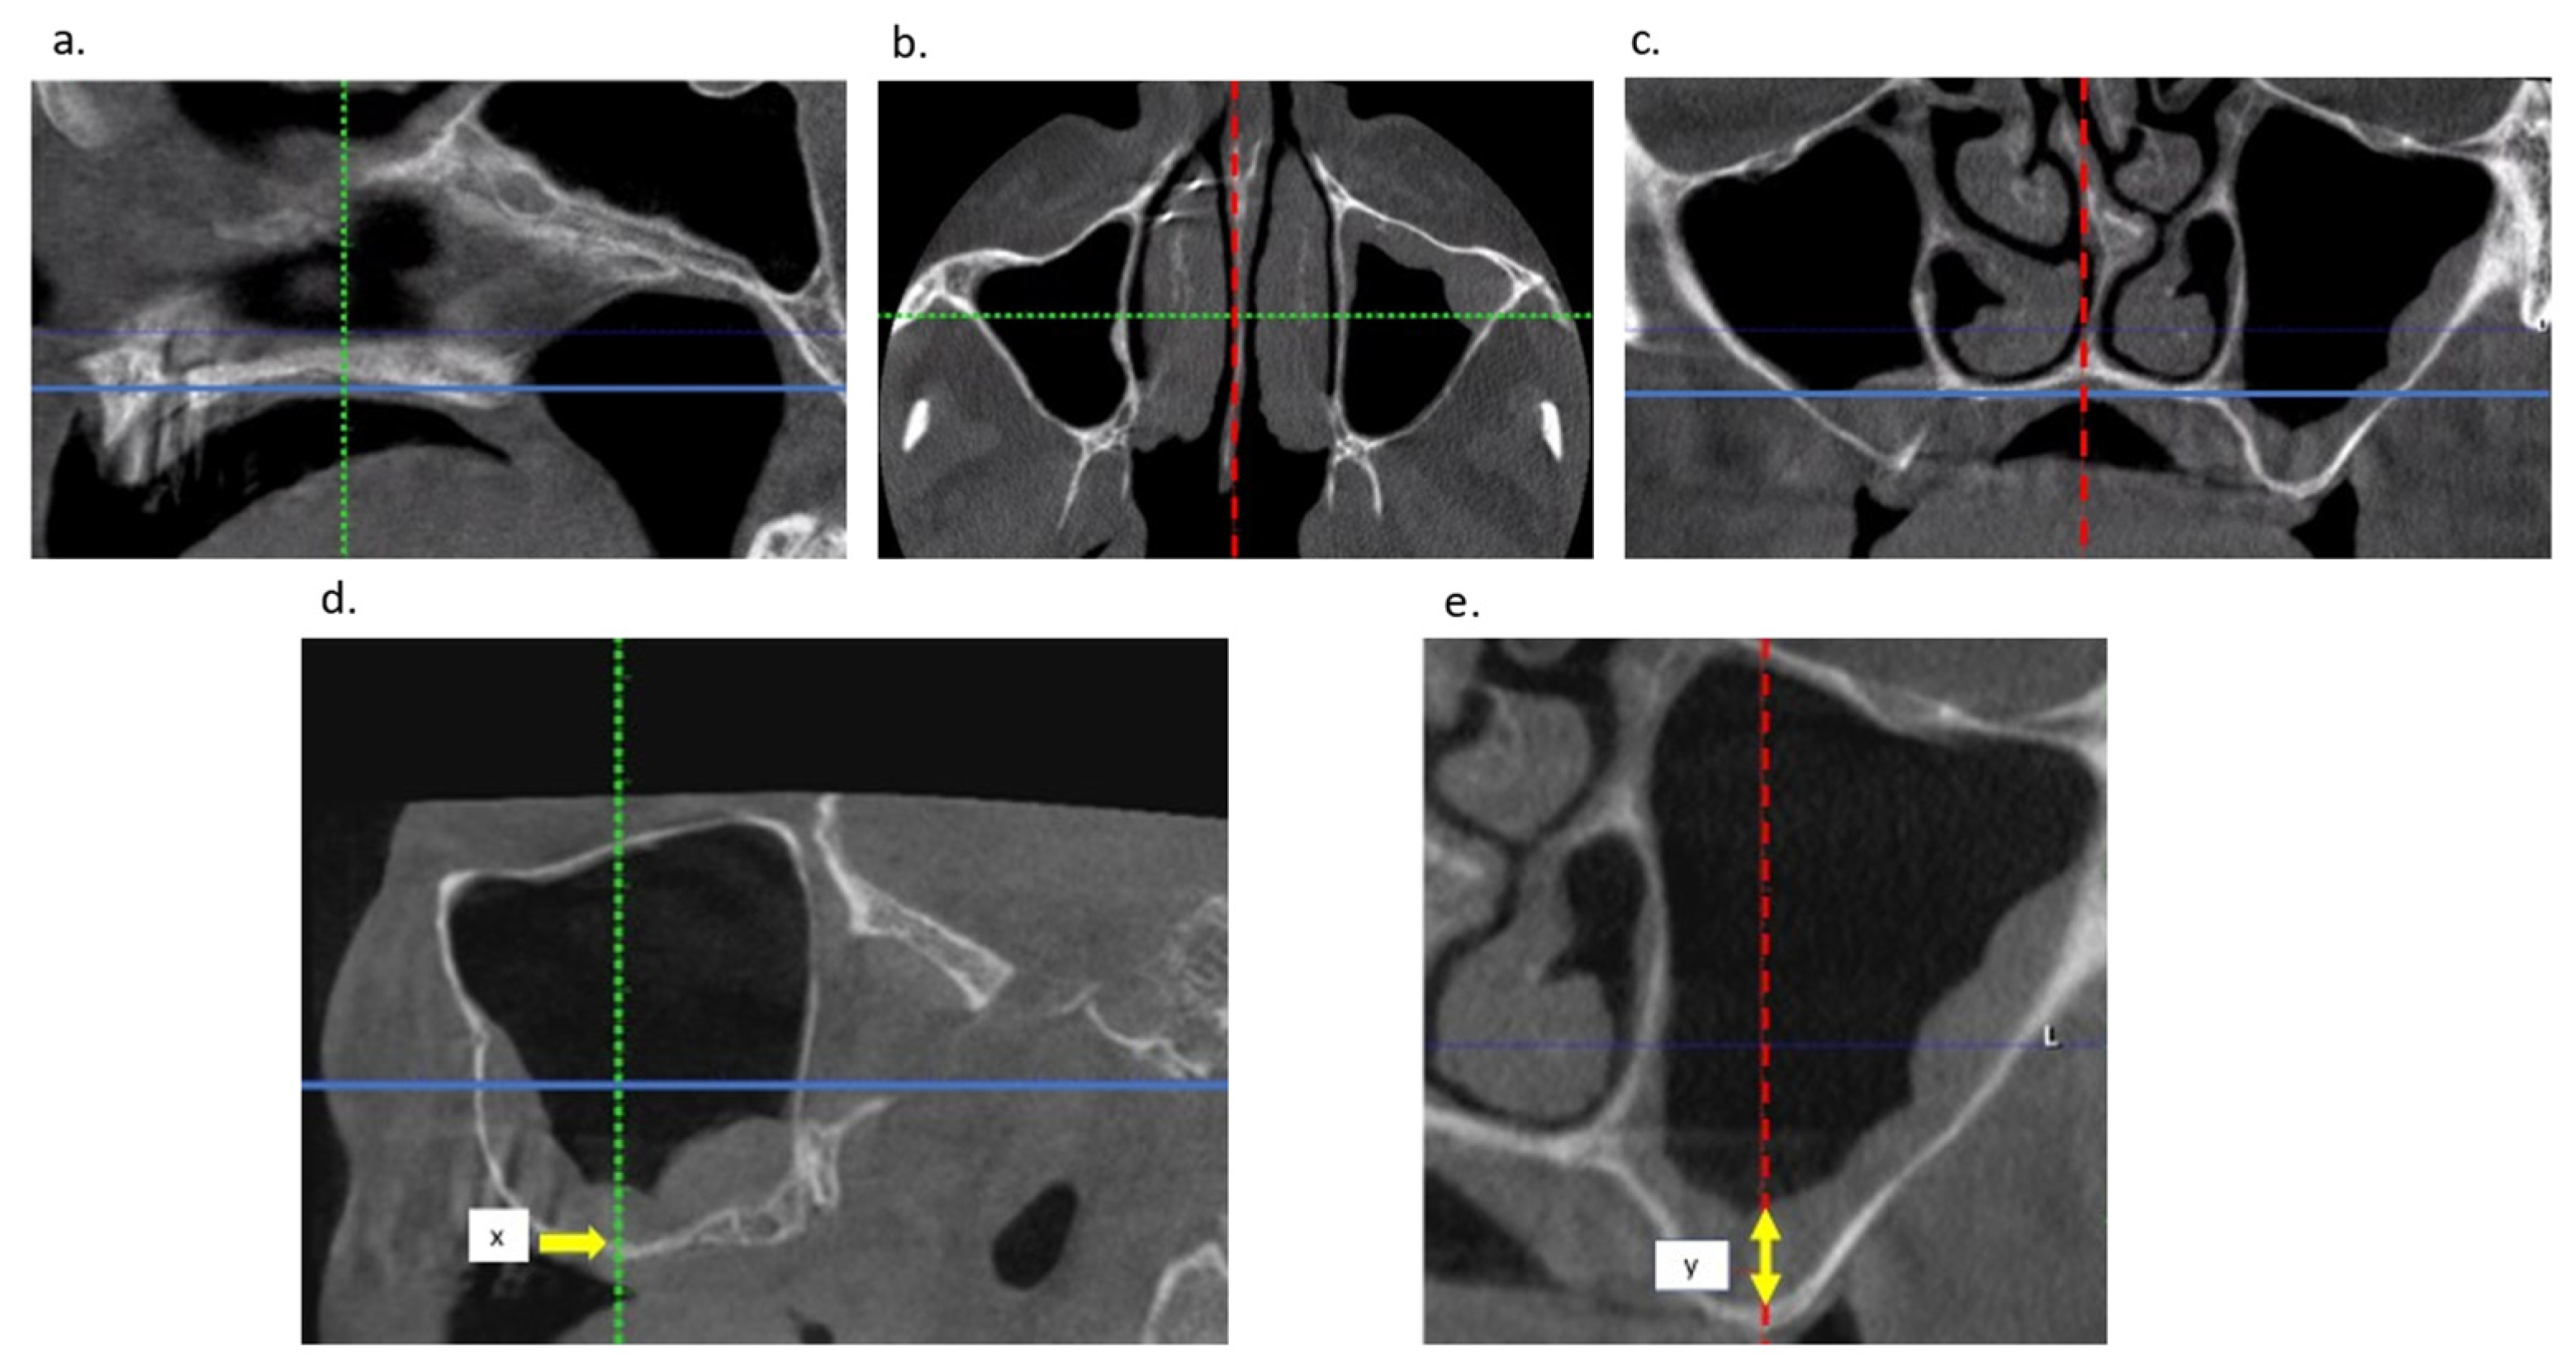

2.2. Radiological Examination

- Van Doorne, L.; Gholami, P.; D’Haese, J.; Hommez, G.; Meijer, G.; De Bruyn, H. Three-Dimensional Radiographic Outcome of Free-Handed Flaplessly Placed Mini Dental Implants in Edentulous Maxillae after 2-Years Function. J. Clin. Med. 2020, 9, 2120. [Google Scholar] [CrossRef] [PubMed]